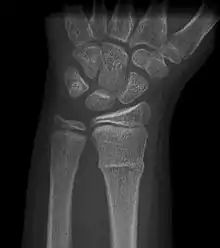

Buckle fracturs can be identified by performing a radiograph. The diagnosis of a torus fracture is made from both anterior/posterior and lateral projections. The typical features include:

- The buckling of cortical bone, which may appear as a small bulge or protuberance in the radius or ulna.

- The bone may have a slight angulation.[8]